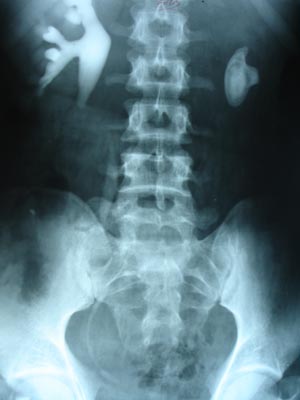

Renal calculas IVP

Urographic media are highly concentrated solution of organically bound iodine. Dye is injected intravenously & films are taken at various interval. The visualization of renal substace is dependant on the amount of contrast reaching the kidneys, wheras the visualization of the collecting system depends mainly on the ability to concentrate urine.